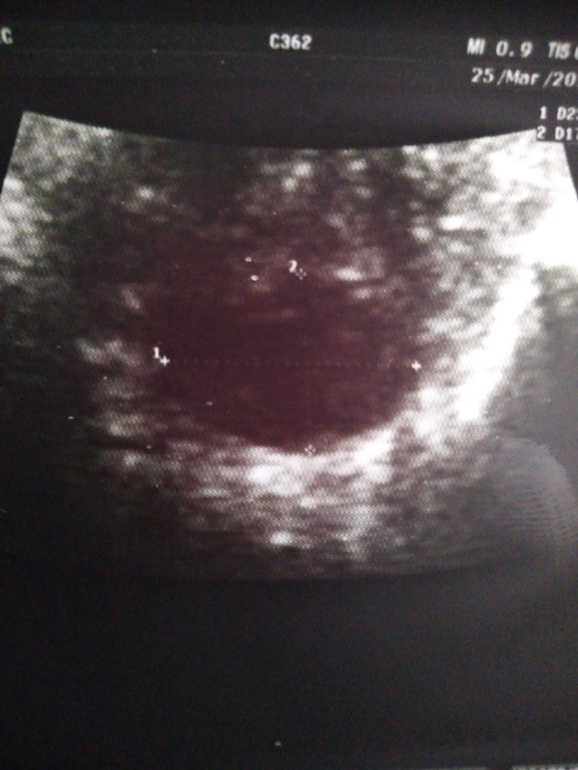

я склоняюсь к кисте желтого тела,у фолликулярной ровные края и она как пузырик,круглая больше...

вот жт